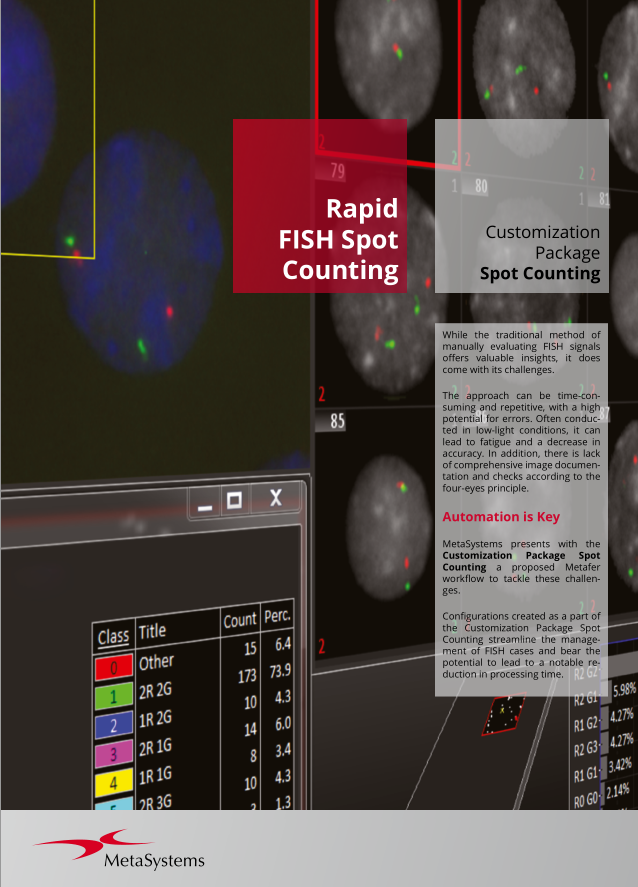

- Review all imaging results in a well-organized image gallery.

- Customize workflows according to your preferences using a flexible classifier-based imaging approach.

Utilizing the Metafer software, imaging systems scan specimens of diverse sizes, employ various contrasting methods and magnifications, and identify, classify, and enumerate cells or other objects. Metafer's modularity and flexible architecture make it proficient in assisting users from various fields with their specific imaging tasks.

Given the variability of each microscopic sample, automated imaging demands flexibility. Metafer's distinctive concept provides an effective solution: user-trainable classifiers accurately establish imaging standards, and by selecting the relevant classifier, the integrated scanning system swiftly transitions to the next task.